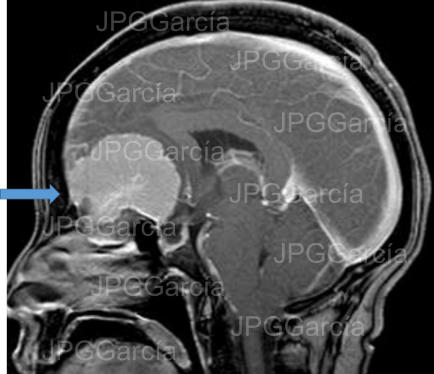

Meningioma del plano esfenoidal Imagen de resonancia magnética corte sagital